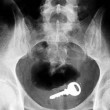

ROMA – Con il sesso i giochi erotici possono essere molto variegati. Questa “compilation” mostra però come a volte quei giochini finiscono male. Ecco infatti svariate radiografie eseguite negli ospedali di tutto il mondo.

Tutte queste persone sono state ricoverate con diversi oggetti incastrati nell’ano e non solo: dal cellulare alle chiavi di casa, passando per proiettili e giocattoli come macchinine e pupazzetti.